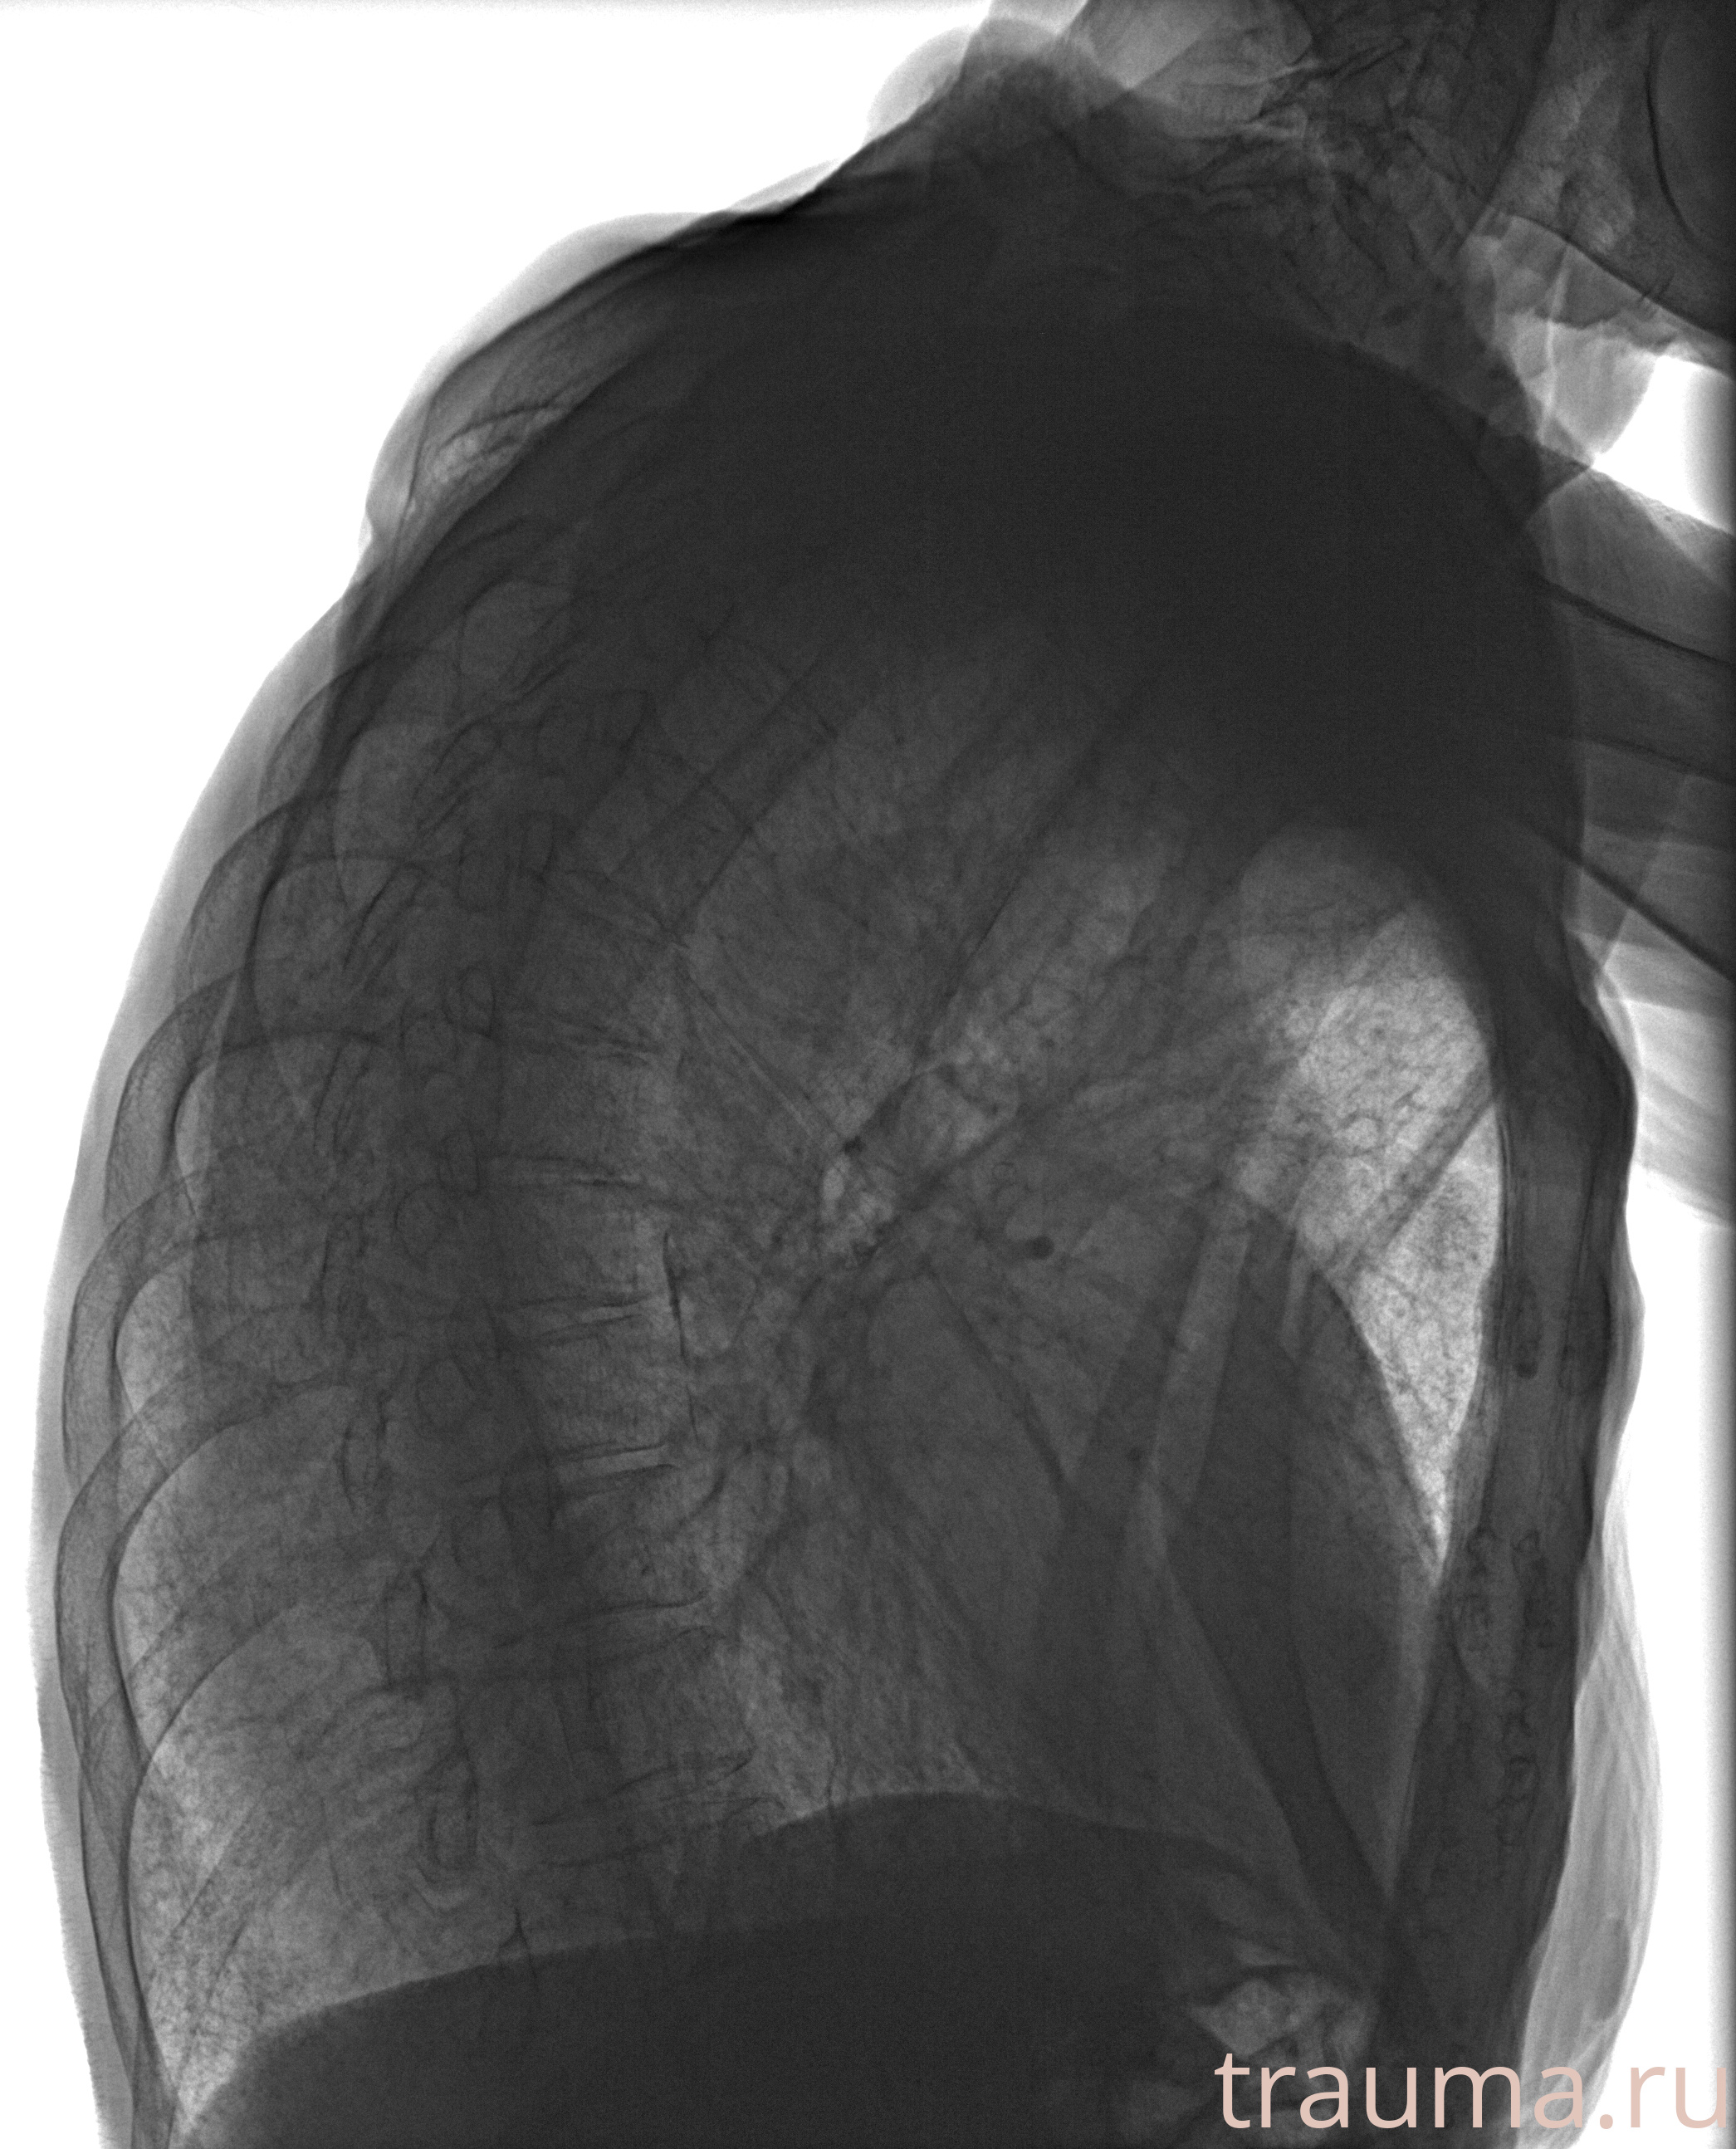

Рентген на дому: по вашему адресу приезжает врач-рентгенолог, травматолог-ортопед с мобильным рентгеновским аппаратом, проводит диагностику травмы или заболевания, делает необходимые рентгенограммы, дает рекомендации по дальнейшему лечению. Получить качественные снимки в домашних условиях возможно благодаря уникальной методике, разработанной МосРентген Центром для института  Склифосовского